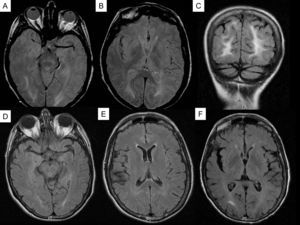

Various physiopathological mechanisms have been suggested, including vasoconstriction, increased perfusion, and endothelial damage. A study of recurrent cases may help us answer some of the unresolved questions about this syndrome. We present the case of a patient with recurrent PRES episodes which were effectively treated with nimodipine. The patient was a 60-year-old female who came to the emergency department in May 2009. She had a history of smoking, high blood pressure, high cholesterol, and ischaemic heart disease. She presented with headache, drowsiness, nausea, vomiting, and aphasic comprehension which had developed over 2 days, coinciding with an attack of hypertension (blood pressure 220/110mmHg). Once the hypertension had been resolved, the patient gradually regained her baseline state and was asymptomatic 48 to 72hours after being admitted. The patient had been treated with chemotherapy during the preceding 2 years for stage IV ovarian adenocarcinoma. Magnetic resonance (MR) scan showed predominantly parietal-occipital white matter lesions with no restrictions in the diffusion sequences. The lesions disappeared one month later (Fig. 1). Following that, the patient presented with 3 similar episodes in January, April, and June 2010; all episodes coincided with a marked increase in blood pressure. The MR scan showed changes similar to those described in PRES, which disappeared once the episode had resolved. The patient discontinued chemotherapy following the first episode and started antihypertensive treatment with beta blockers, ARBs, alpha blockers and diuretics; blood pressure control between episodes was good. Treatment with nimodipine was begun in June 2010; at 15 months of follow-up, no new episodes had occurred.